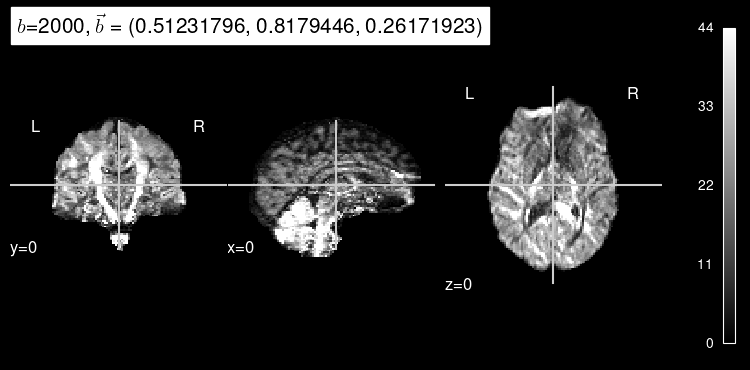

Here’s the original DW map, for reference:

plot_dwi(np.squeeze(data_test[0]), dmri_dataset.affine, gradient=data_test[1]);